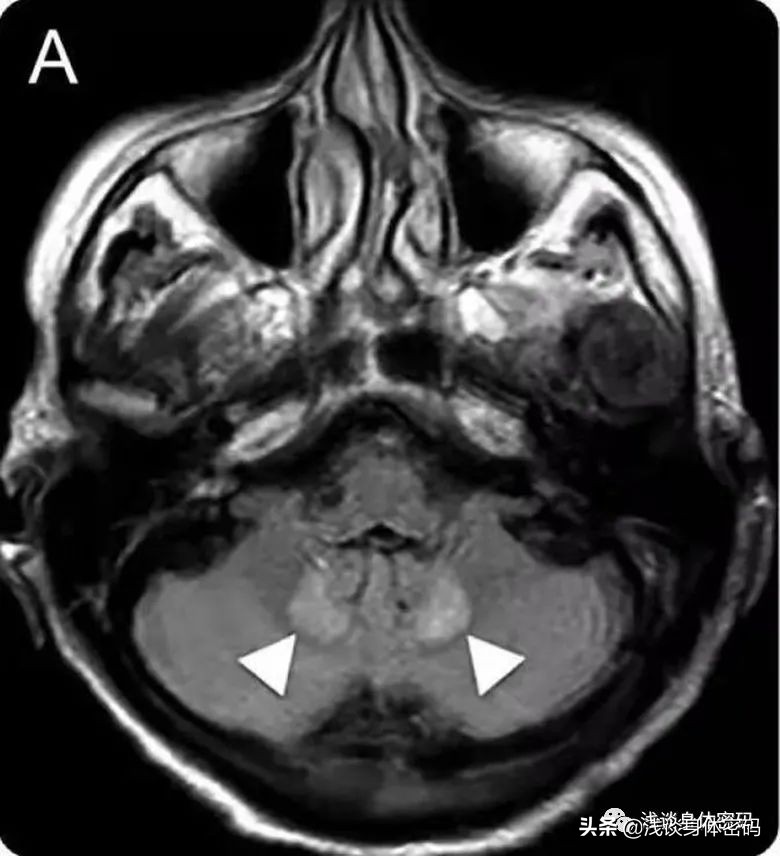

MIE的首选检查方法是头颅MRI,通常显示小脑齿状核附近区域特有的对称性病变,亦可累及胼胝体压部、脑桥被盖部、中脑、脑白质、基底节区等。齿状核对称性病变常用来区分其他原因引起的脑病。

MRI Flair显示双侧小脑齿状核、上丘和导水管周围灰质对称性高信号: